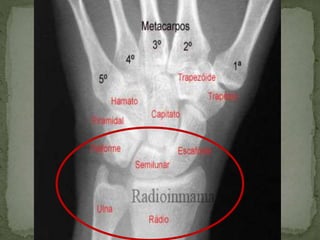

A superfície articular do rádio funciona como um platô, no

qual se articula os ossos do carpo semilunar, escafoide e

A superfície articulardo rádio funciona como um platô, no qual se articula os ossos do carpo semilunar, escafoide e incisura ulnar.